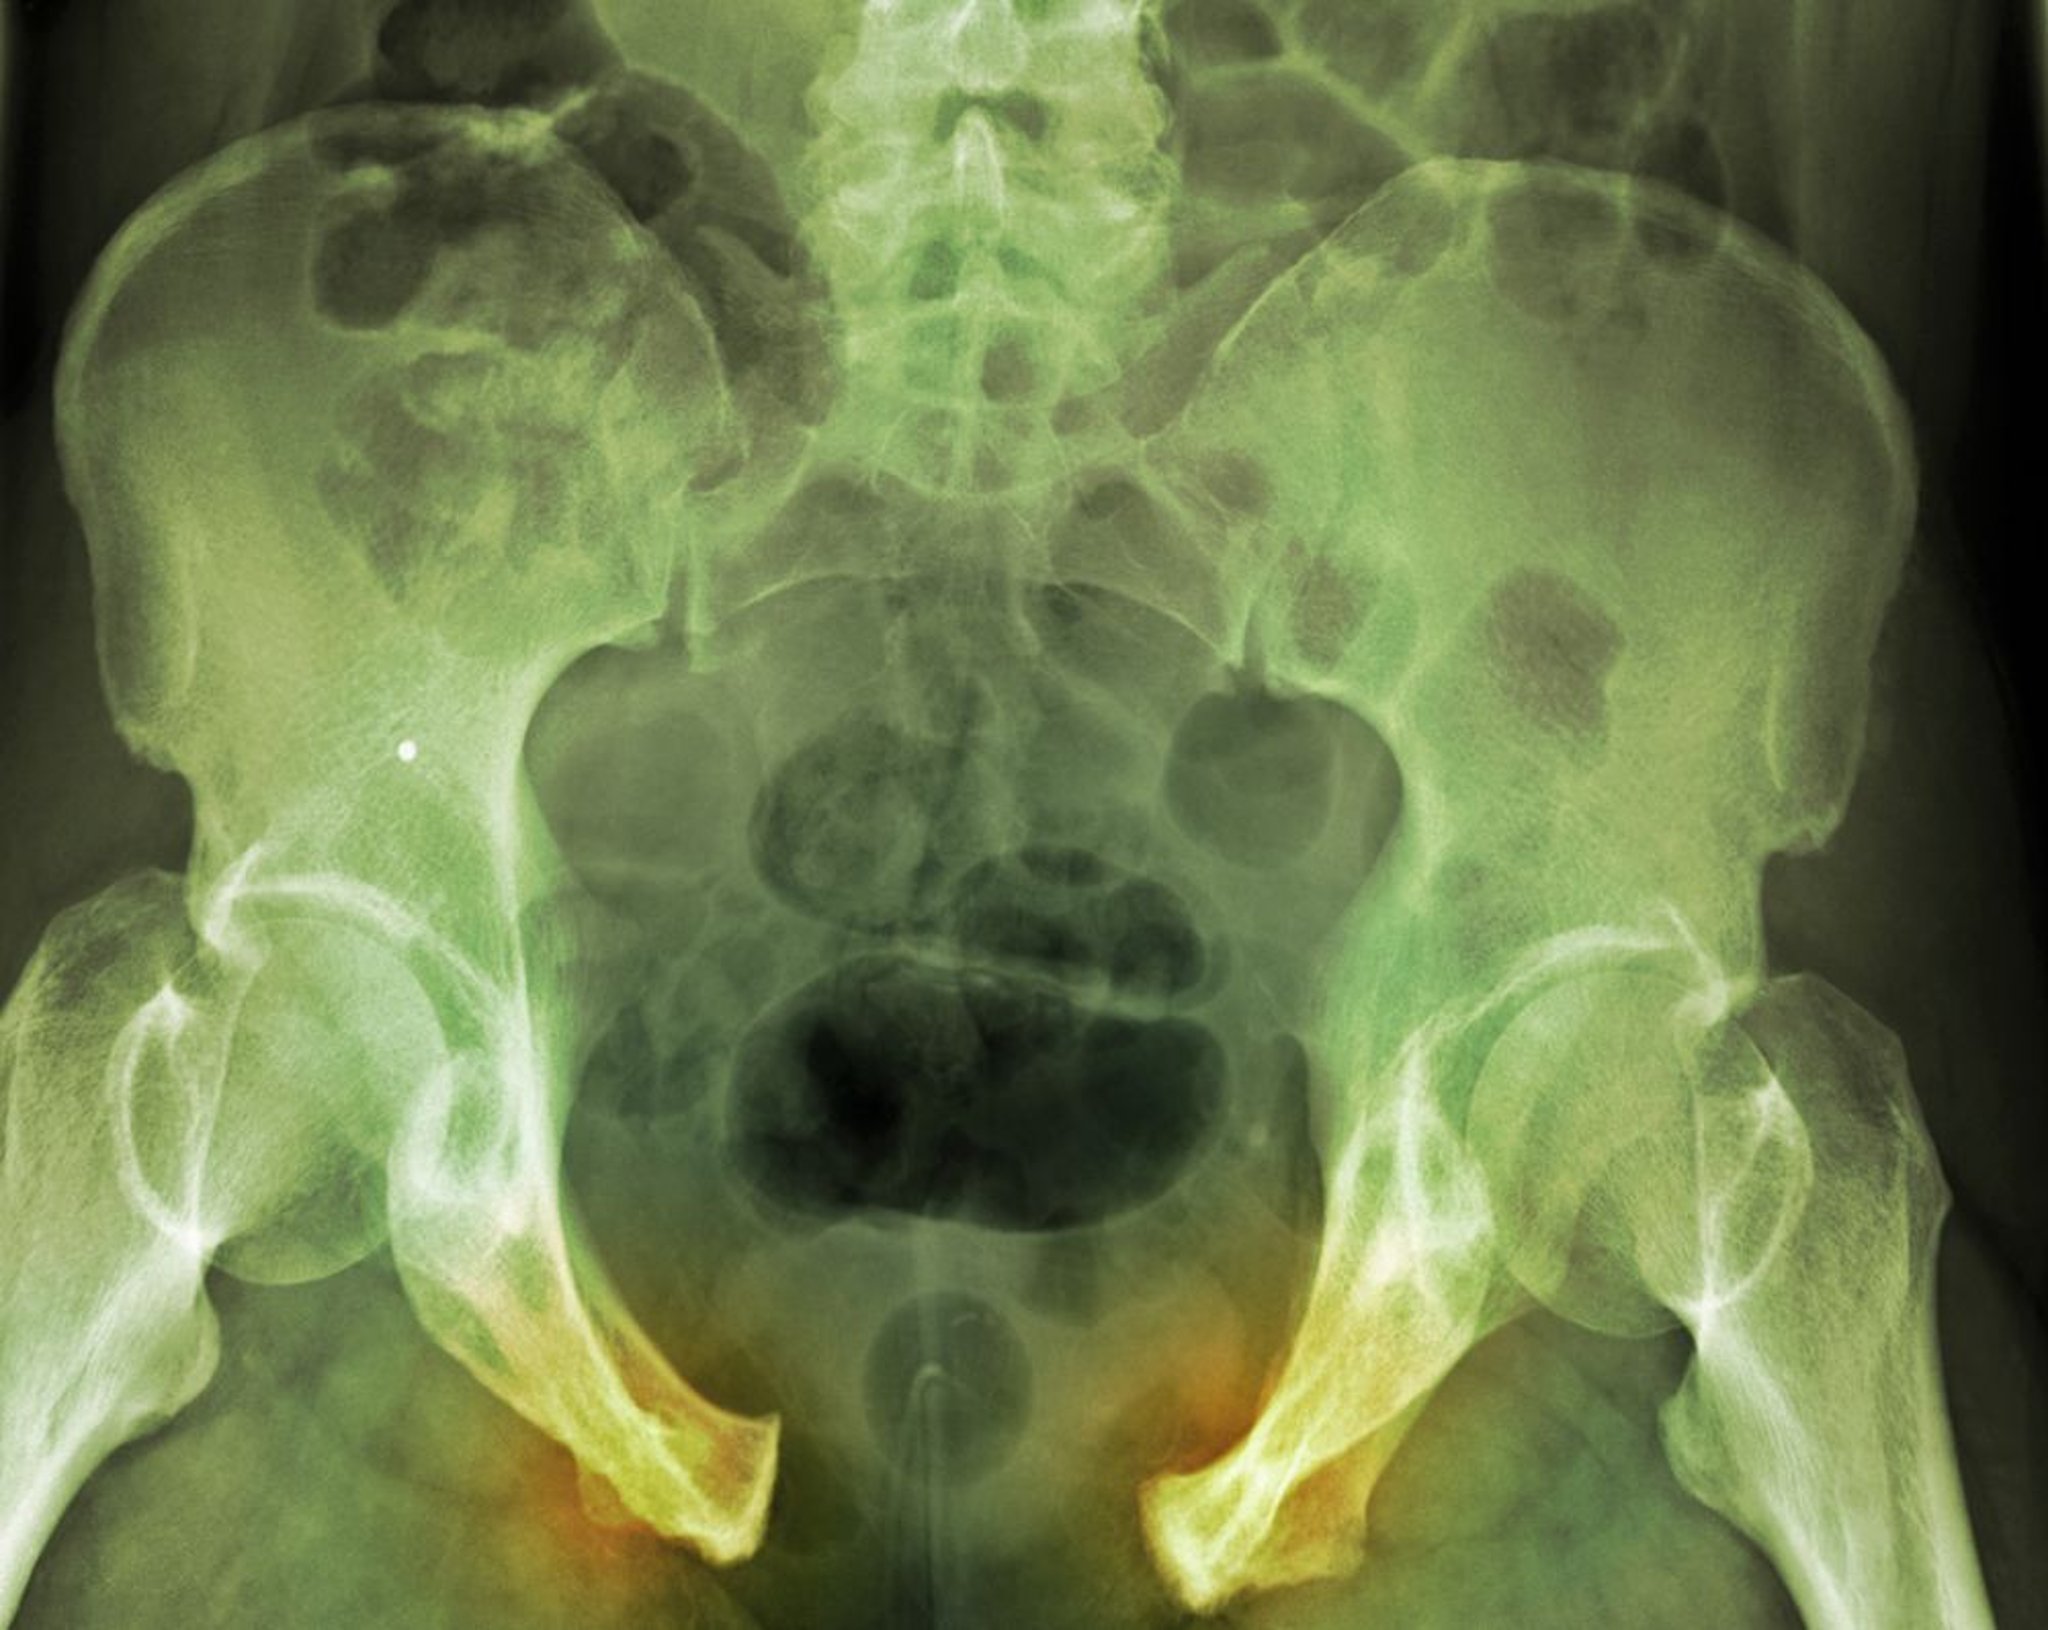

Gãy xương chậu

Trong chấn thương nặng này, đứt đoạn của vành chậu biểu hiện rõ dựa trên dấu hiệu rộng khớp liên kết xương mu và các dây chằng cùng chậu bên phải. Các đường gãy không rõ ràng.